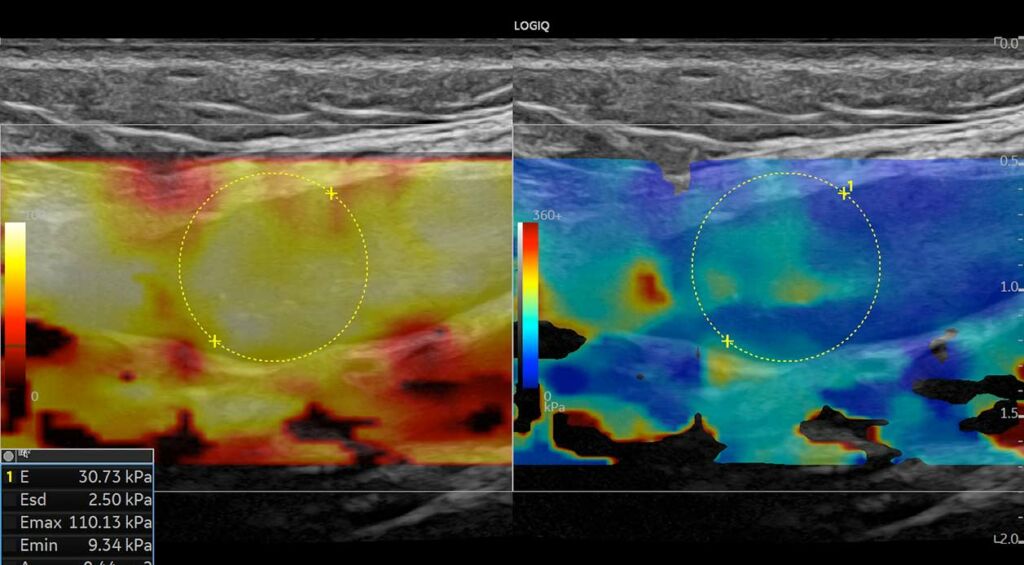

- 2D Shear Wave Ελαστογραφία, για την αξιολόγηση της σκληρότητας των ιστών